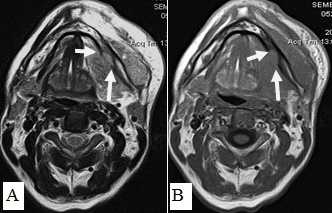

Рис. 11: А. МРТ полости рта, ротоглотки в аксиальной проекции. Рецидив опухоли языка размерами 6,0х6,5 см с распространением на дно полости рта, правую боковую стенку ротоглотки (стрелки). Выявляется переход за среднюю линию; В. Тот же больной. МРТ полости рта, ротоглотки в коронарной проекции. Опухолевый узел показан стрелками. Просвет ротоглотки сужен, деформирован. Опухоль имеет низкий сигнал на Т1-ВИ, аналогичный сигналу от окружающих мышц, при этом размеры опухолевого узла, его объемные характеристики позволяют четко отграничить от интактных тканей. Также отмечается структурная неоднородность патологического образования за счет некроза

При МРТ-исследованиях оценка инфильтрации костной ткани проводилась по следующим показателям: отсутствие типичного гипоинтенсивного сигнала от кортикального слоя на Т1-ВИ и Т2-ВИ, появление сигнала высокой или средней интенсивности на Т1-ВИ и Т2-ВИ, соответствующего опухолевой ткани, появление гипоинтенсивного сигнала на Т1, гиперинтенсивного сигнала на Т2 или Т2 с подавлением сигнала от жировой ткани, что демонстрировало поражение костного мозга (рис. 15).

![Рис. 15. Пациент С.,52 г. МРТ полости рта в аксиальной проекции в режиме Т2-ВИ (А) и Т1-ВИ (В). Рак дна полости рта с распространением на нижнюю челюсть, инфильтрацией мягких тканей щечной, подбородочной области слева. Выявляется деструкция кортикального слоя нижней челюсти слева, поражение костного мозга (стрелки)]()

Рис. 15. Пациент С.,52 г. МРТ полости рта в аксиальной проекции в режиме Т2-ВИ (А) и Т1-ВИ (В). Рак дна полости рта с распространением на нижнюю челюсть, инфильтрацией мягких тканей щечной, подбородочной области слева. Выявляется деструкция кортикального слоя нижней челюсти слева, поражение костного мозга (стрелки)